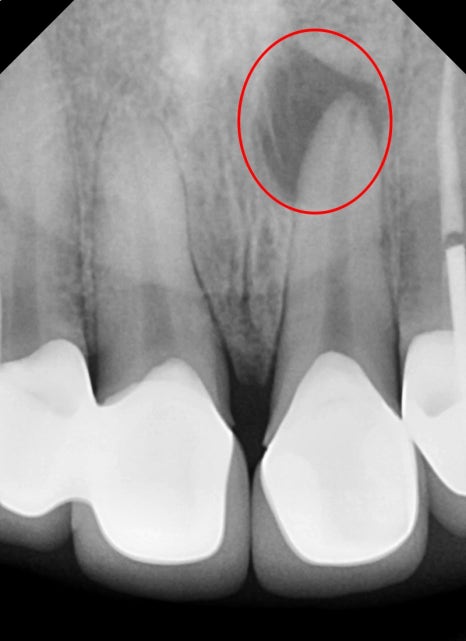

자세히 보기 위해 엑스레이를 찍어보았습니다.

뿌리끝 염증과 측면 쪽 염증 신경치료 후 앞니 보철치료 진행

엑스레이에 선명하게 보일 정도로

이미 안쪽으로 염증이 생긴지 수개월 된것으로 보여집니다.

염증이 생긴 곳의 위치가 일반적이지 않아 CT를 찍어보았습니다.

흔들리지는 않지만 뿌리 주변 뼈가 염증반응으로 인해

많이 소실되어 보입니다.

일반적으로 치아 신경에서 온 염증으로 인한 뼈의 소실은

신경치료 후 치유가 되면 다시 건강한 뼈가 채워주게 됩니다.